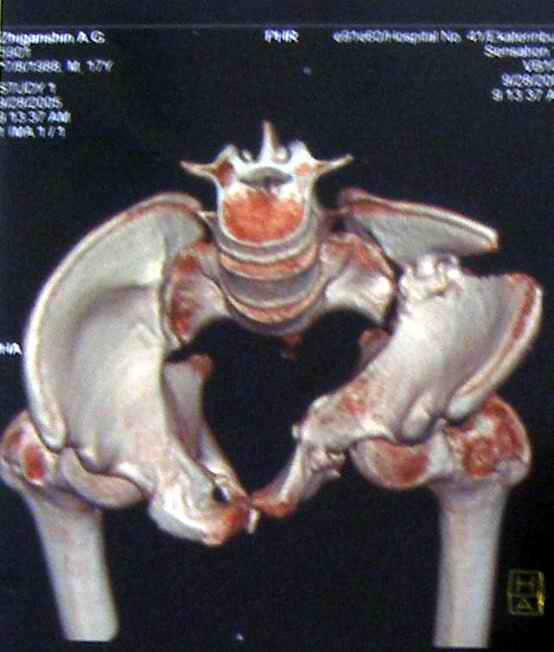

Коллеги, помогите определиться с тактикой лечения пациента. Ув. коллеги, к нам поступил молодой человек 17 лет. Травма в июле 2005- ДТП, т.е. 3 мес назад. Лечился консервативно в "гамаке" 1,5 мес., затем ходьба с костылями без опоры на левую нижнюю конечность, начал на нее опираться 1 нед назад. В настоящее время имеется укорочение порядка 4-5 см, выраженная хромота, передвигается с одним костылем. Кроме того беспокоят боли в пояснично-крестцовой области при ходьбе, неудобство при сидении, невозможность лежать на спине "на жестком", а также на левом боку (субъект худощавый, боль в области крыла) хромота, длительное пребывание на ногах невозможно. На функциональных снимках большой подвижности нет (не привожу из-за плохого качества). Учитывя наличие участков сращений, помогите опредилиться с тактикой. Наш план пока такой: 1. выполнить остеотомии в участках сращений 2.постепенно аппаратом низвести смещенную половину таза. 3.выполнить внутренний остеосинтез передних и задних отделов. Будем признательны за ваш взгляд на тактику леченияэтого больного, а так же на такие проблемы как: места остеотомий, возможные варианты компоновки аппарата, выбор имплантатов для последующего вмешательства.

Уважаемый коллега. Не знаю, прооперировали-ли вы больного или нет, но глядя на Р-граммы захотелось поделится сосбражениями. Укорочение конечности на 4-5 см конечно-же нужно устранить. Вы хотите выполинть остетомию мест сращения, любопытно каким образом? Если пользоваться широкими доступами, то возможно выпонить репозицию открыто и фиксировать погружнными конструкциями как Вы и планируете после репозиции в аппарате. Тем самым устранить укорочение конечности, может быть конечно не оплностью но на 2-3 см то точно. Закрыто же выполнить остеотомию сращений наверное возможно сзади, спереди я бы не рискнул, а лонные кости рубить надо. Что касается лечения аппаратом, то я ученик "вашей школы" что вашим аппаратом можно устранить смещения полностью. Но стоит ли подвергать пациента длительному дискомфорту и повышать риск воспалительных осложнений? Учитывая Ваш опыт лечения таких повреждений таза я бы остановился на одномоментной открытой репозиции и остеосинтезе. С уважением Гринь Алексей.